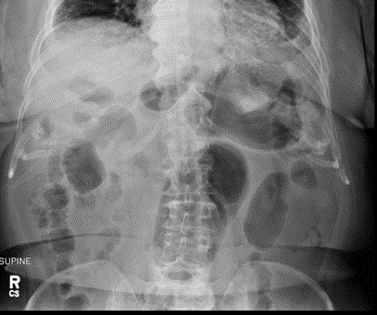

Initial radiography usually reveals a herniated stomach above the diaphragm, with air fluid levels seen inside the stomach. A chest X-ray may show a retrocardiac gas-filled viscus that can help confirm the diagnosis. Abdominal imaging may reveal a distended viscus in the upper abdomen. An organ axial volvulus may show a horizontal orientation of the stomach with a single air-fluid level and a paucity of distal gas [3]. A mesenteroaxial volvulus may show plain abdominal plain radiographic findings showing a spherical stomach on supine images with two air-fluid levels on erect images with the antrum positioned superior to the fundus [3]. Endoscopy is also used in the evaluation and treatment of a patient with gastric volvulus. Endoscopies are sometimes used to evaluate upper abdominal issues and as a result can reveal signs of gastric volvulus as a byproduct [12].